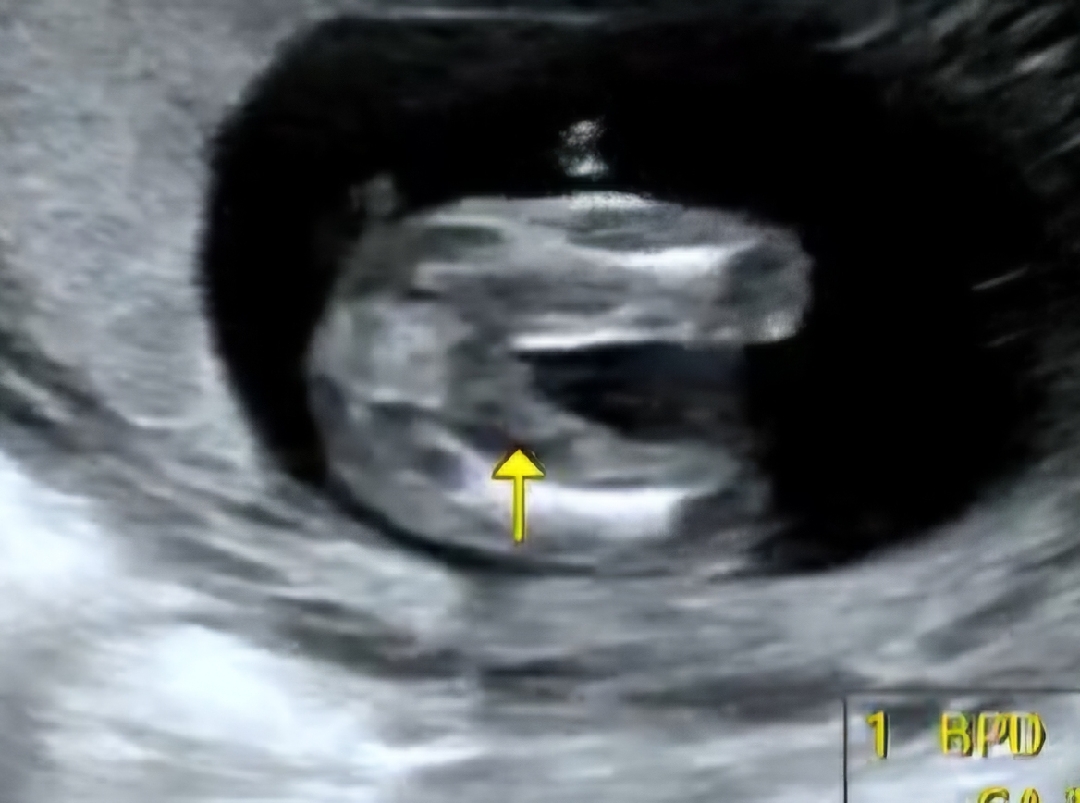

15주에 이정도면 여아같아요!

초음파 보는중에 남편이 참지못하고 성별을 여쭤봤더니 흔쾌히 초음파 각도를 틀어서 아기 다리쪽을 봐주시고는 남아다 여아다 말씀하는 대신 "허허 없네요" 라고하시더라구요 ㅋㅋ 다른분들이 보기에도 공쥬같나요?? 하루하루 힘든데 또 초음파 보면 너무 귀엽고 노산의 장점도 있는거같아요. 신체적으로는 힘 들지만 정신적으로는 어느정도 성숙해져있고, 간절하게 원할 때 축복받고 태어날 아가를 생각하면. 건강하게만 와다오. 엄빠랑 지지고볶으며 살게.

공주네용

없는거같긴해요 ㅎㅎ